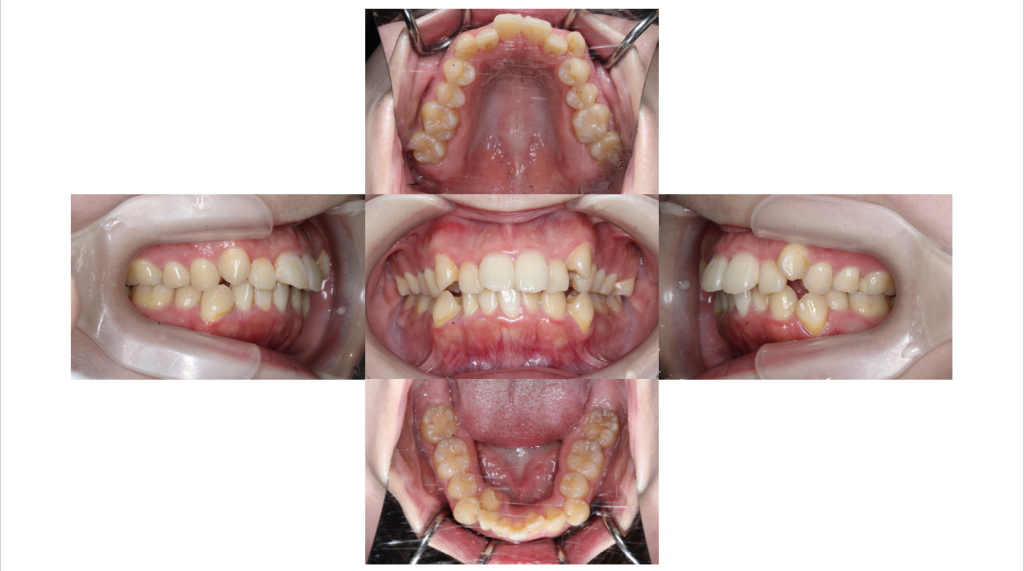

初診

叢生・裏側矯正の症例矯正治療開始前の口腔内写真です。